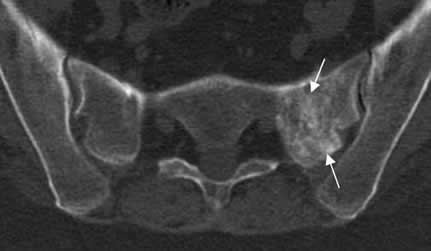

Fig 59. Fractura de stress.

TAC axial. Zona de fibrosis en el alerón izquierdo del sacro, resultado de reparación por fractura de stress.